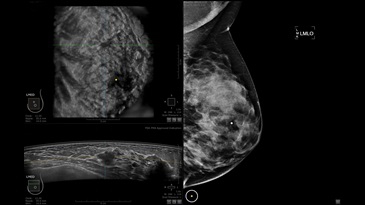

GE INVENIA ABUS – это современный УЗИ аппарат, который создан для точной и эффективной диагностики сканирования с высокой плотностью молочных желез. Выявляемость патологий раковых и предраковых стадий заболевания составляет 55%, что в конечном счете позволяет ставить врачу точные и своевременные диагнозы. Традиционные методы использования маммографии не показывают такой выявляемости, ограничиваясь лишь 3-38%.

УЗИ-аппарат GE INVENIA ABUS позволяет проводить максимально операторонезависимые процедуры, что значительно снижает риск неправильной постановки диагноза и сопутствующие издержки на обработку информации. Система готовит отчет в течение 3-х минут после сканирования, это безусловное преимущество по сравнению с обычным УЗИ сканером.

• Отображение объемных 3D ультразвуковых изображений, которые состоят из традиционных поперечных и воссозданных коронарных и сагиттальных проекций

• Стандартизованная ориентация изображения: «толстый срез» в коронарной плоскости; поперечная; сагиттальная плоскость; радиальный и антирадиальный поворот изображения; просмотр исключительно области интереса

• Изменяемая толщина среза: 0,5 - 10,0 мм (шаг 0,5 мм)

• Срез: 0,5 - 2,0 мм (шаг 0,5 мм)